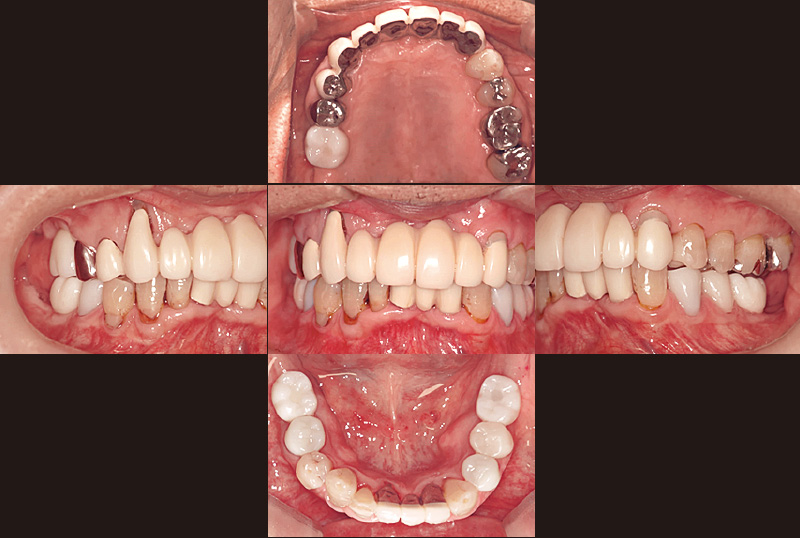

症例の患者さんは、初診時74歳の男性です(図1, 2)。この時は、別の一眼レフカメラで撮影していますが、現在は初診時の5枚法写真は全て歯科衛生士が「ルナビューショット」で撮影しています。一眼レフカメラは女性にとっては少し重たいですし、ミラーを持ちながら片手で撮影するには、ある程度の技術が必要です。また、患者さんにお見せするためパソコンにインポートする際にも一手間が必要です。「ルナビューショット」はとにかく簡単、手軽に撮影でき、「TrinityCore Pro」と連携して、ミラーモードも気にせず自動配置してくれます。オペの様子もアシストする歯科衛生士が随時撮影して、オペ後に患者さんにお見せしながら処置内容を説明しています。

症例の患者さんは、奥様の介護があり毎日忙しくされていることもあってか、とにかくプラークコントロールが不良で、改善の兆しが見えませんでした。初診から6年が経過し、その間補綴治療を行ってきましたが、相変わらず磨き残しは目立っていました(図3)。そのため、染め出し後に「PrimescanConnect」でスキャンしたデータをお見せしたところ、「こんなにも磨き残しがあるとは思ってなかった」と、とても驚かれ、それ以降セルフケアの意識が向上し、磨き残しは大幅に減少しました(図4~6)。

図1 初診時74歳男性。₆の脱離を主訴に来院された。歯を残すことを希望され、前歯部はブリッジ、臼歯部には義歯治療を行った。(一眼レフカメラにて撮影) -

図3 その後下顎に2本(₆ ₆)、上顎に1本(₆)のインプラントを埋入。写真は初診から6年後の染め出し写真。プラークコントロールが不良で、常に磨き残しが見られた。 -

図4 初診から6年後。染め出し後に「PrimescanConnect」によるデジタルスキャンデータをお見せすると、残存プラークの多さに大変驚かれた。 -

図5 図4から1か月半後に再度染め出しを行ったところ、ポンティック部分の歯頸部を中心に磨き残しが見られた。 -

図6 デジタルスキャンから約2か月半後の口腔内の状態。 -